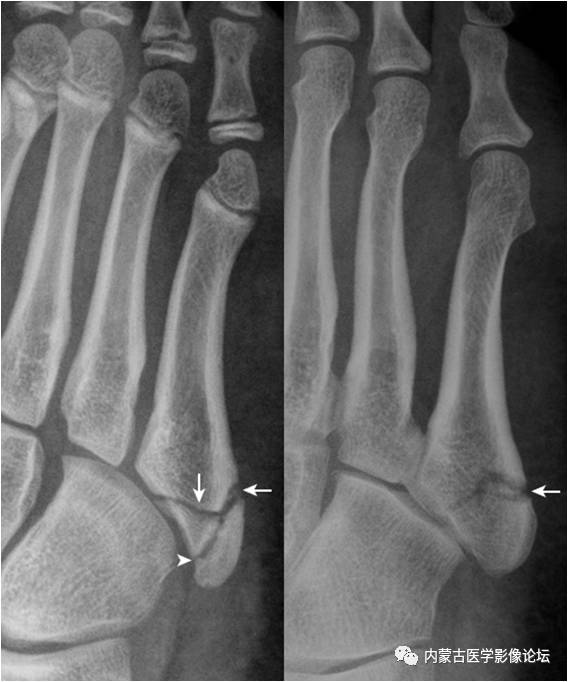

16.第5跖骨粗隆骨化中心:第5跖骨粗隆骨化中心(箭),形态多样,A(女,10岁)为线样且不连续,B(男,13岁)为多发(箭与箭头),C(男,12岁)为边缘光整,D(男,11岁)为内缘粗糙伴裂隙。需与撕脱骨折鉴别,其与粗隆长轴近似平行,而撕脱骨折为腓骨短肌肌腱牵拉所致,骨折线多为横行。

31.第5跖骨粗隆骨折:第5跖骨粗隆处见横行、纵向透亮线,横行透亮线(箭)为骨折线,纵向透亮线(箭头)为骨骺与骨间的软骨连接投影。撕脱骨折线为横行走向是与骨骺连接线的重要鉴别点。(右图,女,5岁;左图,男13岁)